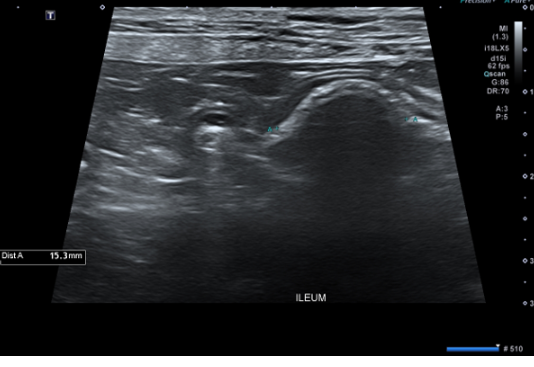

Ultrasound에서 small intestine 내 foreign body가 확인되었고 Intestinal foreign body로 인한 mechanical obstruction이 강하게 의심됩니다.